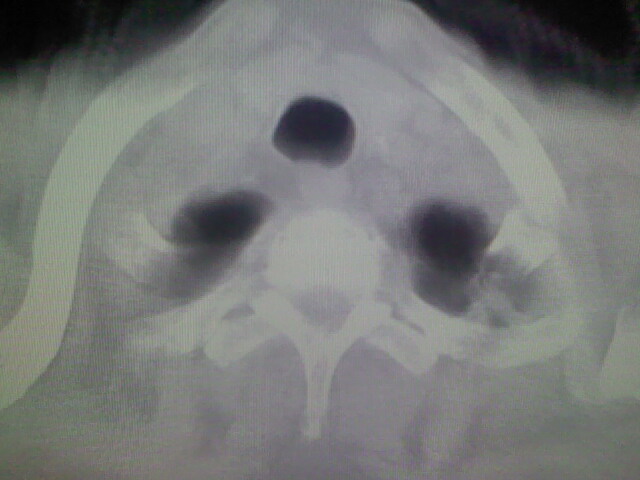

1)考虑右肺上叶周围型肺癌并纵隔及右颈部淋巴结转移,肝脏多发性转移。2)肺气肿。3)冠状动脉及主动脉钙化。

1)考虑右肺上叶周围型肺癌并纵隔及右颈部淋巴结转移,肝脏多发性转移。2)肺气肿。3)冠状动脉及主动脉钙化。支持!另:胃内病变不好确定,建议行胃镜!

1、右肺上叶周围型肺癌并纵隔、颈部淋巴结转移,肝多发转移灶。